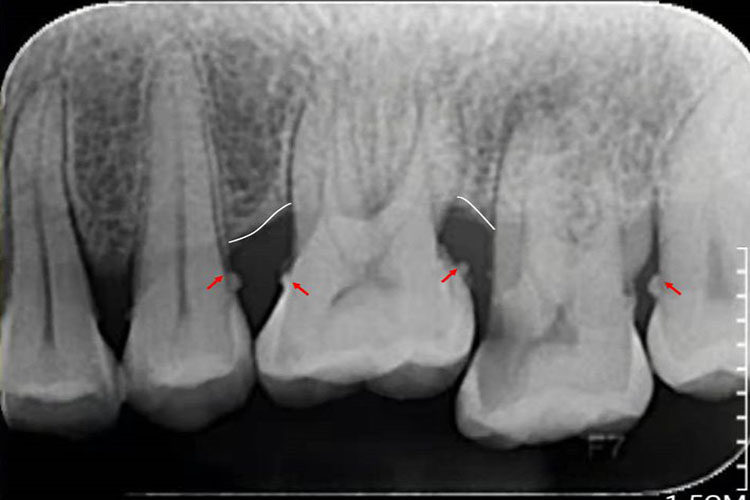

牙结石根据其沉积部位和性质分为龈上牙结石和龈下牙结石两种。龈下牙结石位于龈缘以下、龈袋或牙周袋内的根面上,肉眼不能直视,可用探针探查,或通过影像学检查,方能知其沉积部位和沉积量。龈下牙结石在任何牙位上都可形成,但以牙齿邻面和舌侧面较多。